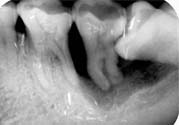

智齒是第三大臼齒,對(duì)相鄰的第二磨牙有重要影響。由于大多數(shù)智齒是前傾阻生的,約呈45度角頂在第二磨牙上,從而形成一個(gè)牙冠夾角,容易嵌塞食物,久之導(dǎo)致第二磨牙齲壞,甚至牙髓炎,就算沒有那么嚴(yán)重也會(huì)影響第二磨牙的壽命。